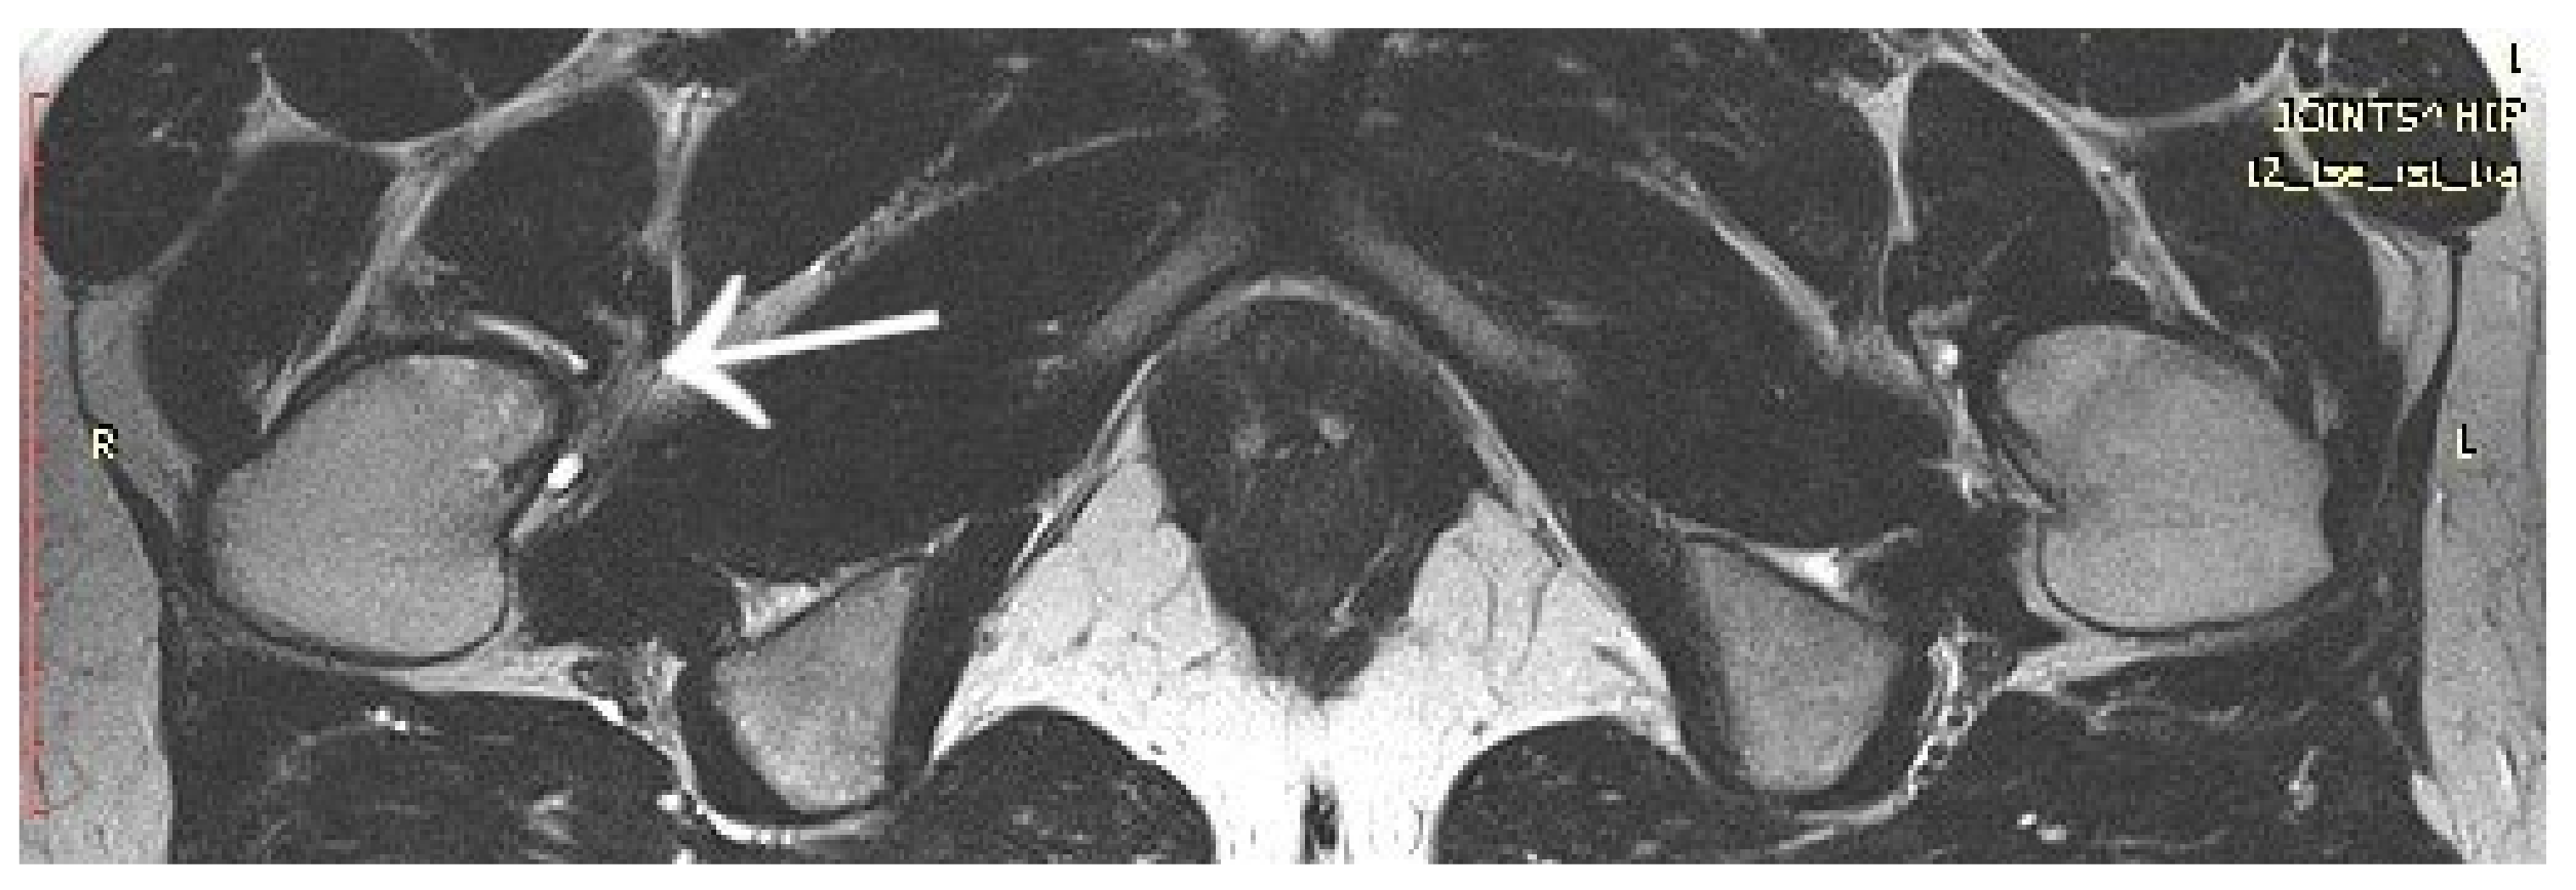

3.1. Case 1: OO Masking as Femoroacetabular Impingement (FAI)